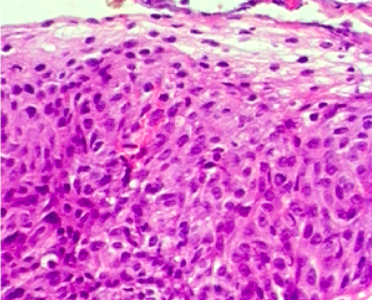

非典型性增生表现为增生的细胞大小不一,核大深染,核浆比例增大,核分裂像增多,但一般不见病理性核分裂;细胞层次增多、排列较乱,极性消失。如下图:

2. 原位癌(carcinoma in situ)

原位癌是指异型增生的细胞在形态和生物学特性上与癌细胞相同,常累及上皮的全层,但没有突破基底膜向下浸润。